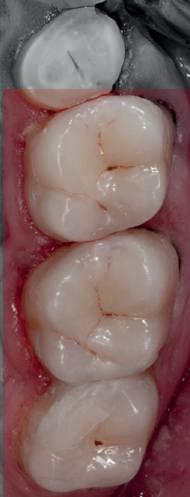

HYBRID COMBINATION RESTAURATIONS

Vonlay-uri: o alternativă conservatoare estetică la coroanele cu acoperire totală